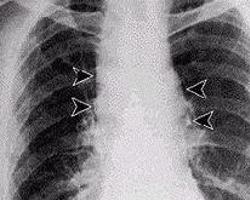

肺炭疽[1](pulmonary anthrax)是炭疽杆菌所致的急性传染病。原系食草动物传染病,人因接触病畜及其产品或食用病畜的肉类而被感染。最常见为皮肤炭疽,表现为皮肤坏死和黑痂,亦可吸入感染引起肺炭疽,误食感染可致肠炭疽,可以继发炭疽杆菌败血症。